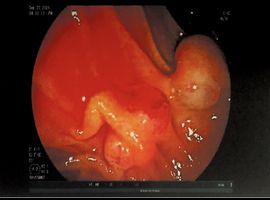

Citation: Wordekemper J, Sigman K, et al. Intraductal Papillary Mucinous Neoplasm Disguised as Pyrosis and Hyperglycemia: A Case Report. Clin Image Case Rep J. 2022; 3(12): 208.